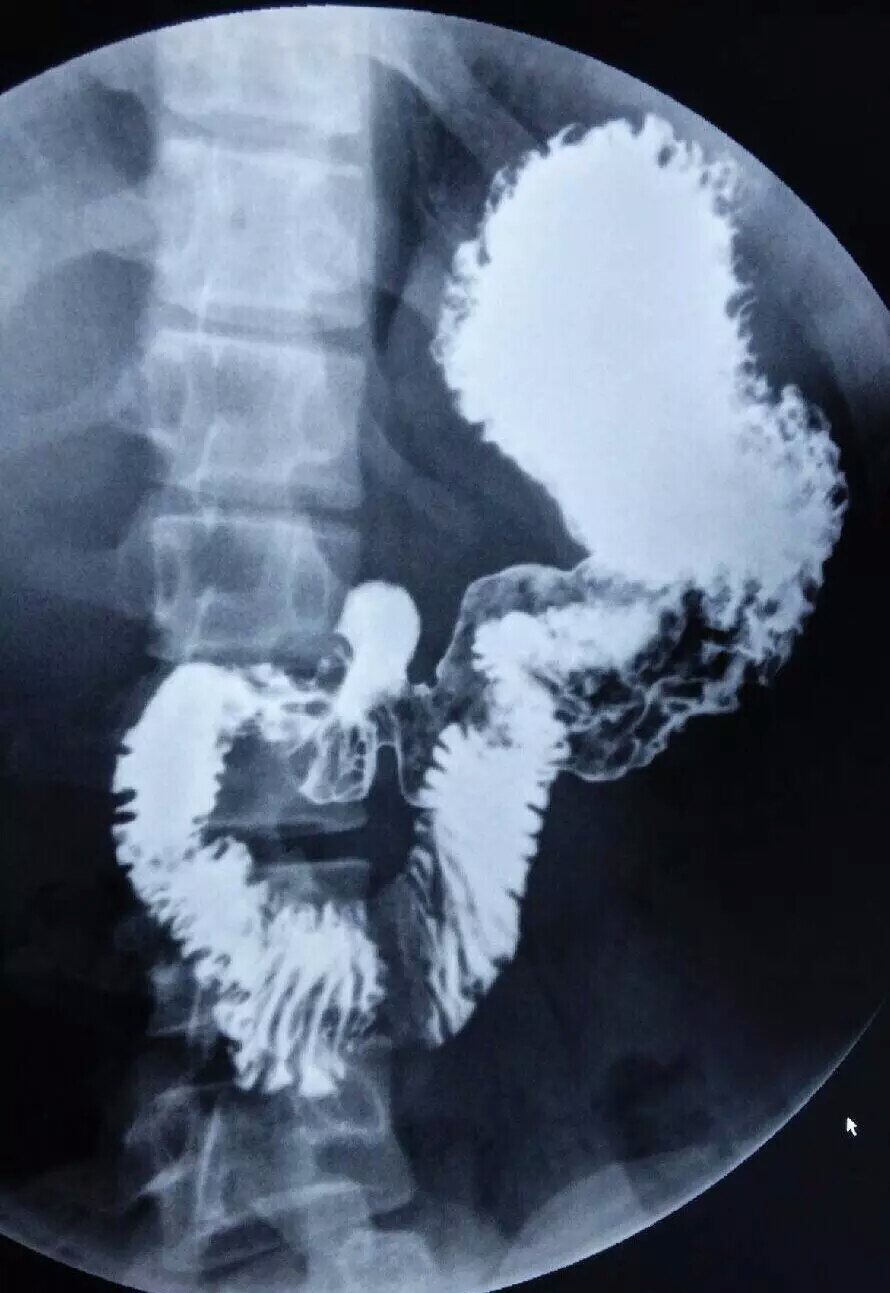

术前上消化道造影显示胃体肿瘤.

患者术前上消化道造影